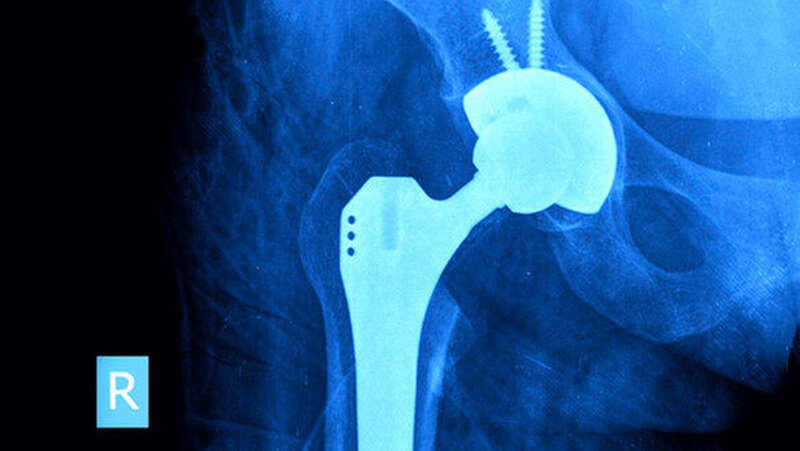

Endoprothesen: Antibiotika-Prophylaxe vor Zahn-OP

Die Expertengruppe um Privatdozent Dr. med. Parham Sendi vom Universitätsklinik für Infektiologie in Bern empfiehlt vor der Implantation einer Gelenkprothese eine zahnärztliche Begutachtung. Dadurch könnten potenzielle Infektionsherde frühzeitig entdeckt und behandelt werden. Zudem sollten Zahnärzte den Zahnstatus regelmäßig beurteilen und Patienten auf die tägliche Mundhygiene hinweisen. Bei Patienten mit schlechter Mundgesundheit und suboptimaler Mundhygiene sei es ratsam, eine zahnmedizinische Untersuchung und allenfalls eine Fokussanierung durchzuführen